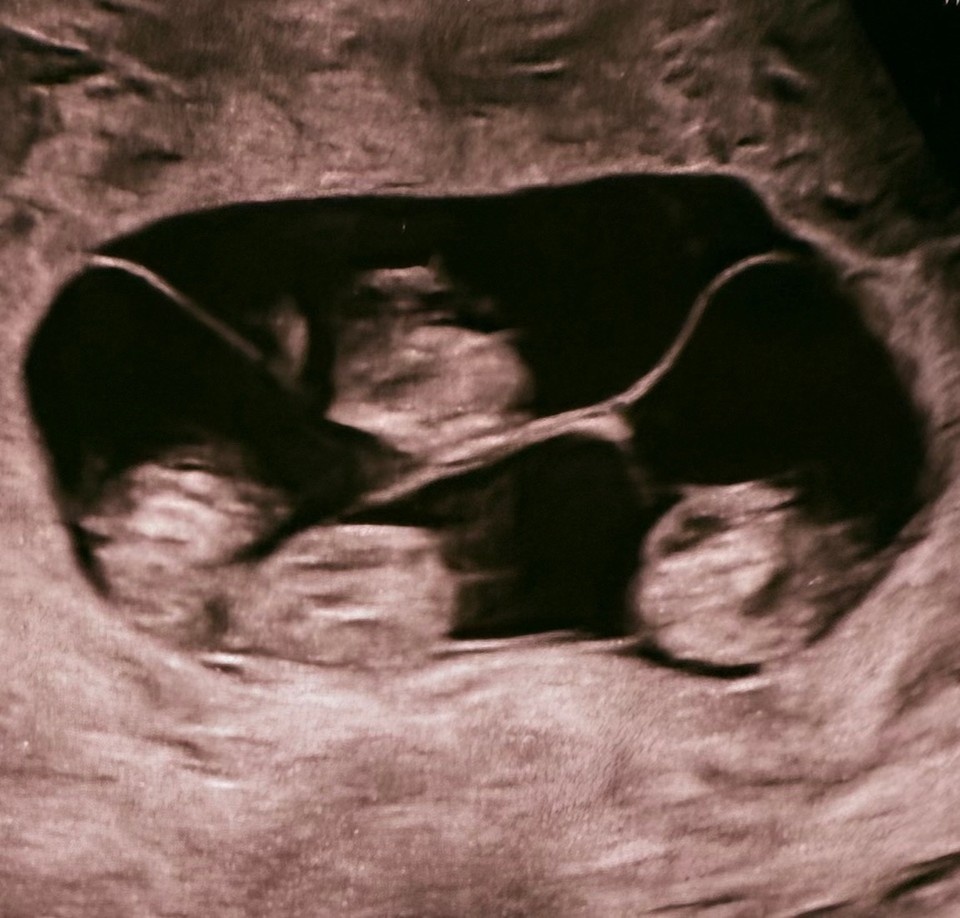

Один случай на 15 миллионов: Четыре однояйцевые девочки-близняшки родились в Петербурге

- По расчетам, монохориальная, то есть однояйцевая, четверня встречается один раз на 15,5 миллиона родов. Детей удалось доносить до 32 недель. Для четверни это очень хороший срок. Вес новорожденных составил от 1360 до 1640 граммов, рост - от 37 до 41 сантиметра, - рассказал врач.

Случай в Петербурге уникален вдвойне. У всех четырех девочек одна общая плацента - это называется монохориальной беременностью. Такое бывает крайне редко.